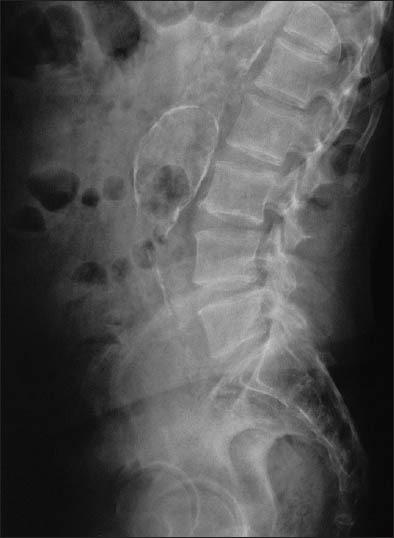

Diagnosis of chronic inflammatory syndrome is often a challenge. In dialysis patients, this condition leads to resistance to recombinant human erythropoietin (rHuEPO). We here report a case of a 72-year-old male undergoing chronic hemodialysis and developed rHuEPO resistance without any obvious etiology. Investigations showed a partially thromosed aneurysm of the infrarenal aorta. Antiplatelet therapy was started with a satisfactory outcome.

慢性炎症综合征的诊断常常具有挑战性。在透析患者中,这种情况会导致对重组人促红细胞生成素(rHuEPO)产生抵抗。我们在此报告一例72岁男性慢性血液透析患者,该患者出现了rHuEPO抵抗且无任何明显病因。检查显示肾下腹主动脉有部分血栓形成的动脉瘤。开始抗血小板治疗,结果令人满意。